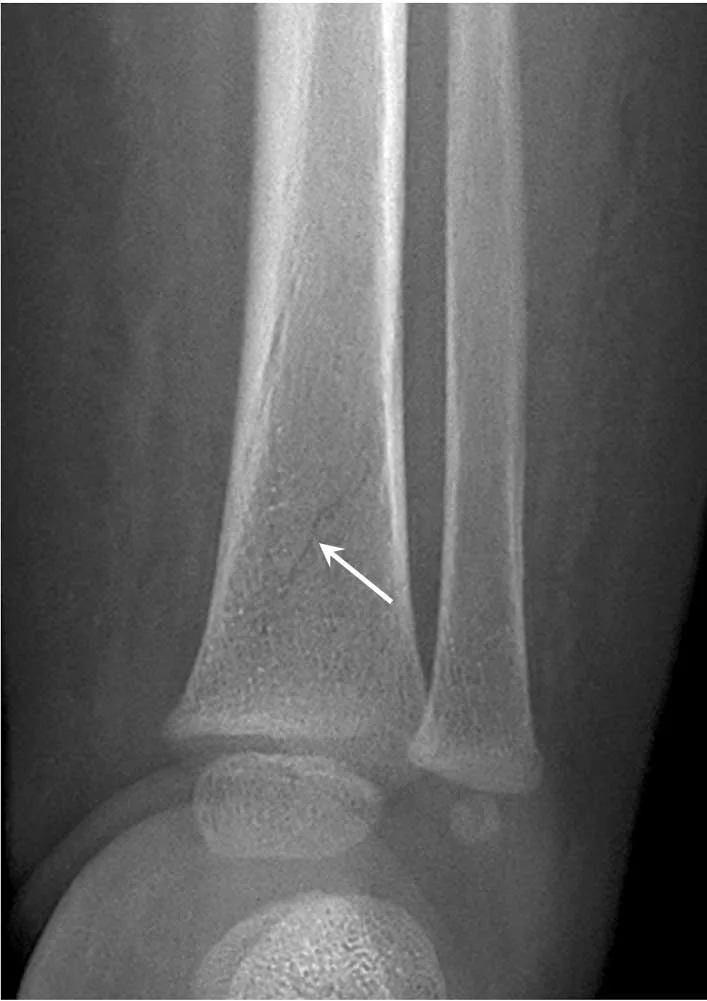

Les fractures diaphysaires des os longs se produisent souvent de manière accidentelle chez l’enfant. Chez un petit qui commence à marcher, une fracture en « cheveu » du tibia (toddler’s fracture des Anglo-Saxons) peut ainsi survenir (fig. 17.4). Celle-ci correspond à une fracture spiroïde isolée, non déplacée, du tiers distal de la diaphyse tibiale. Diverses variantes ont été décrites depuis sa description princeps [3] : fracture oblique du tiers distal de la diaphyse tibiale, fracture spiroïde du tiers moyen de la diaphyse tibiale, fracture sous-périostée à radiographies normales. Ce type de fracture est banal et ne doit pas alerter.

Fig. 17.4 Fracture en « cheveu » du tibia distal chez un enfant âgé de 13 mois. La solution de continuité est très fine (flèche). Ce type de fracture peut survenir à l’apprentissage de la marche et ne doit pas faire suspecter une maltraitance